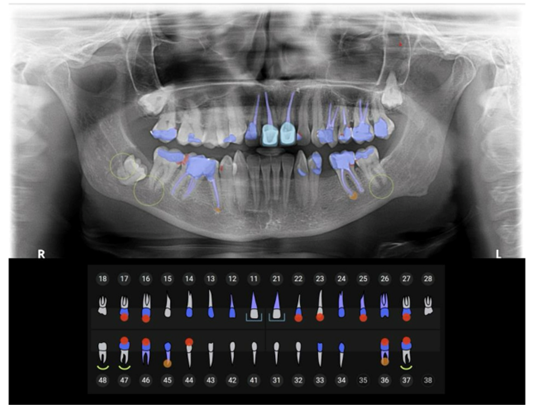

AI-powered platforms such as Pearl, Overjet, and Denti.AI analyze 2D (bitewings, panoramic) and 3D (CBCT) dental radiographs with remarkable precision. These systems can detect interproximal and occlusal caries, periapical lesions, periodontal bone loss, root fractures, and restorative margins.